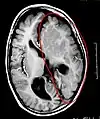

Imágenes

Cerebro enfermo, antes de la hemisferectomía